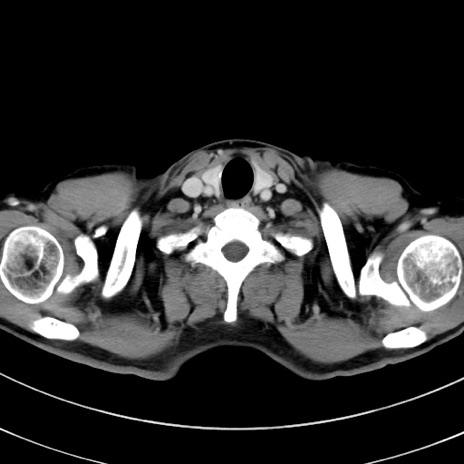

症例8(横断像)

【症例】 60歳代男性

【主訴】 黒色吐物

【現病歴】 4日前から嘔気自覚、2日前の朝食後にも嘔気あり、自分で手で嘔吐反射起こし嘔吐したところ血が混ざっていたため受診。

【既往歴】 5年前汎発性腹膜炎を伴う急性虫垂炎で手術、高血圧、前立腺肥大症、高脂血症

【身体所見】 腹部正中に手術癩痕あり 腹部平坦・軟圧痛なし膨満感あり

【データ】WBC 8400、CRP 4.54